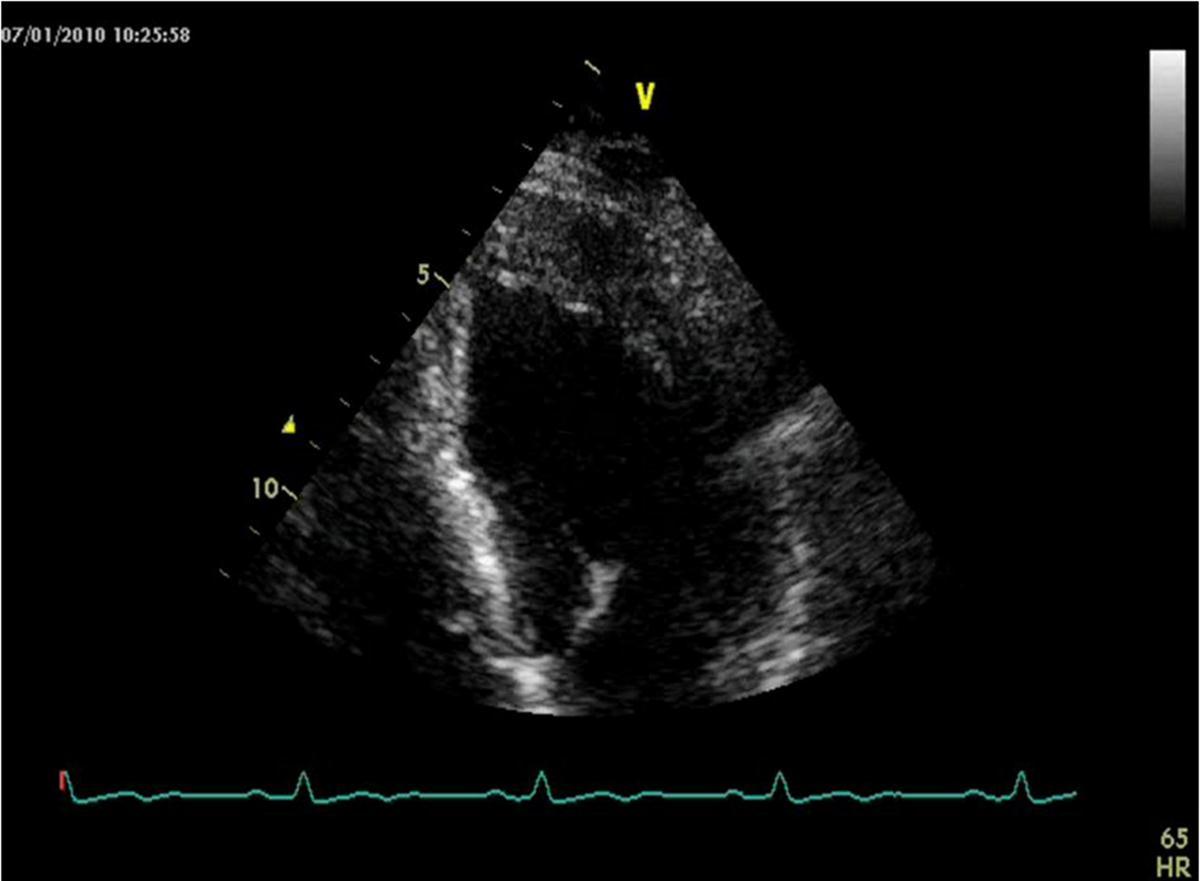

He was asymptomatic, in good general conditions, blood pressure 120/80 mmHg, no murmurs. The electrocardiogram showed sinus bradycardia (55 bpm) and left ventricular hypertrophy signs (deep and symmetric negative T waves in DI, aVL, V2 till V6). Echocardiogram (VIVID 7, 2-4 MHz probe) showed non classical apical hypertrophic cardiomyopathy (Figure 2), localized at anterior, lateral and posterior apex (septum was preserved), with no obliteration of apical cavity. By mean of color-Doppler evaluation, we observed multiple and thin color flows from LAD draining into apical region. Pulse-wave Doppler temporization was exclusively diastolic (Figure 3). Stress echocardiography with accelerate dipyridamole resulted negative for inducible ischemia and no variation in fistula flow was detectable. Inguinal hernia intervention was safely performed and the patient was advised to undergo periodical cardiologic controls.

Figure 2.Echocardiogram image of non classical apical hypertrophic cardiomyopathy of the patient.